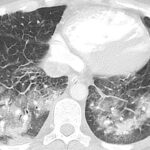

O diagnóstico de embolia pulmonar é feito com base na suspeita clínica e na realização de exames complementares. O principal exame para confirmar o diagnóstico é a angiotomografia de artérias pulmonares, um tipo especial de tomografia de tórax com contraste. Outros exames, como cintilografia pulmonar, ultrassom e angiografia, também podem ser utilizados.